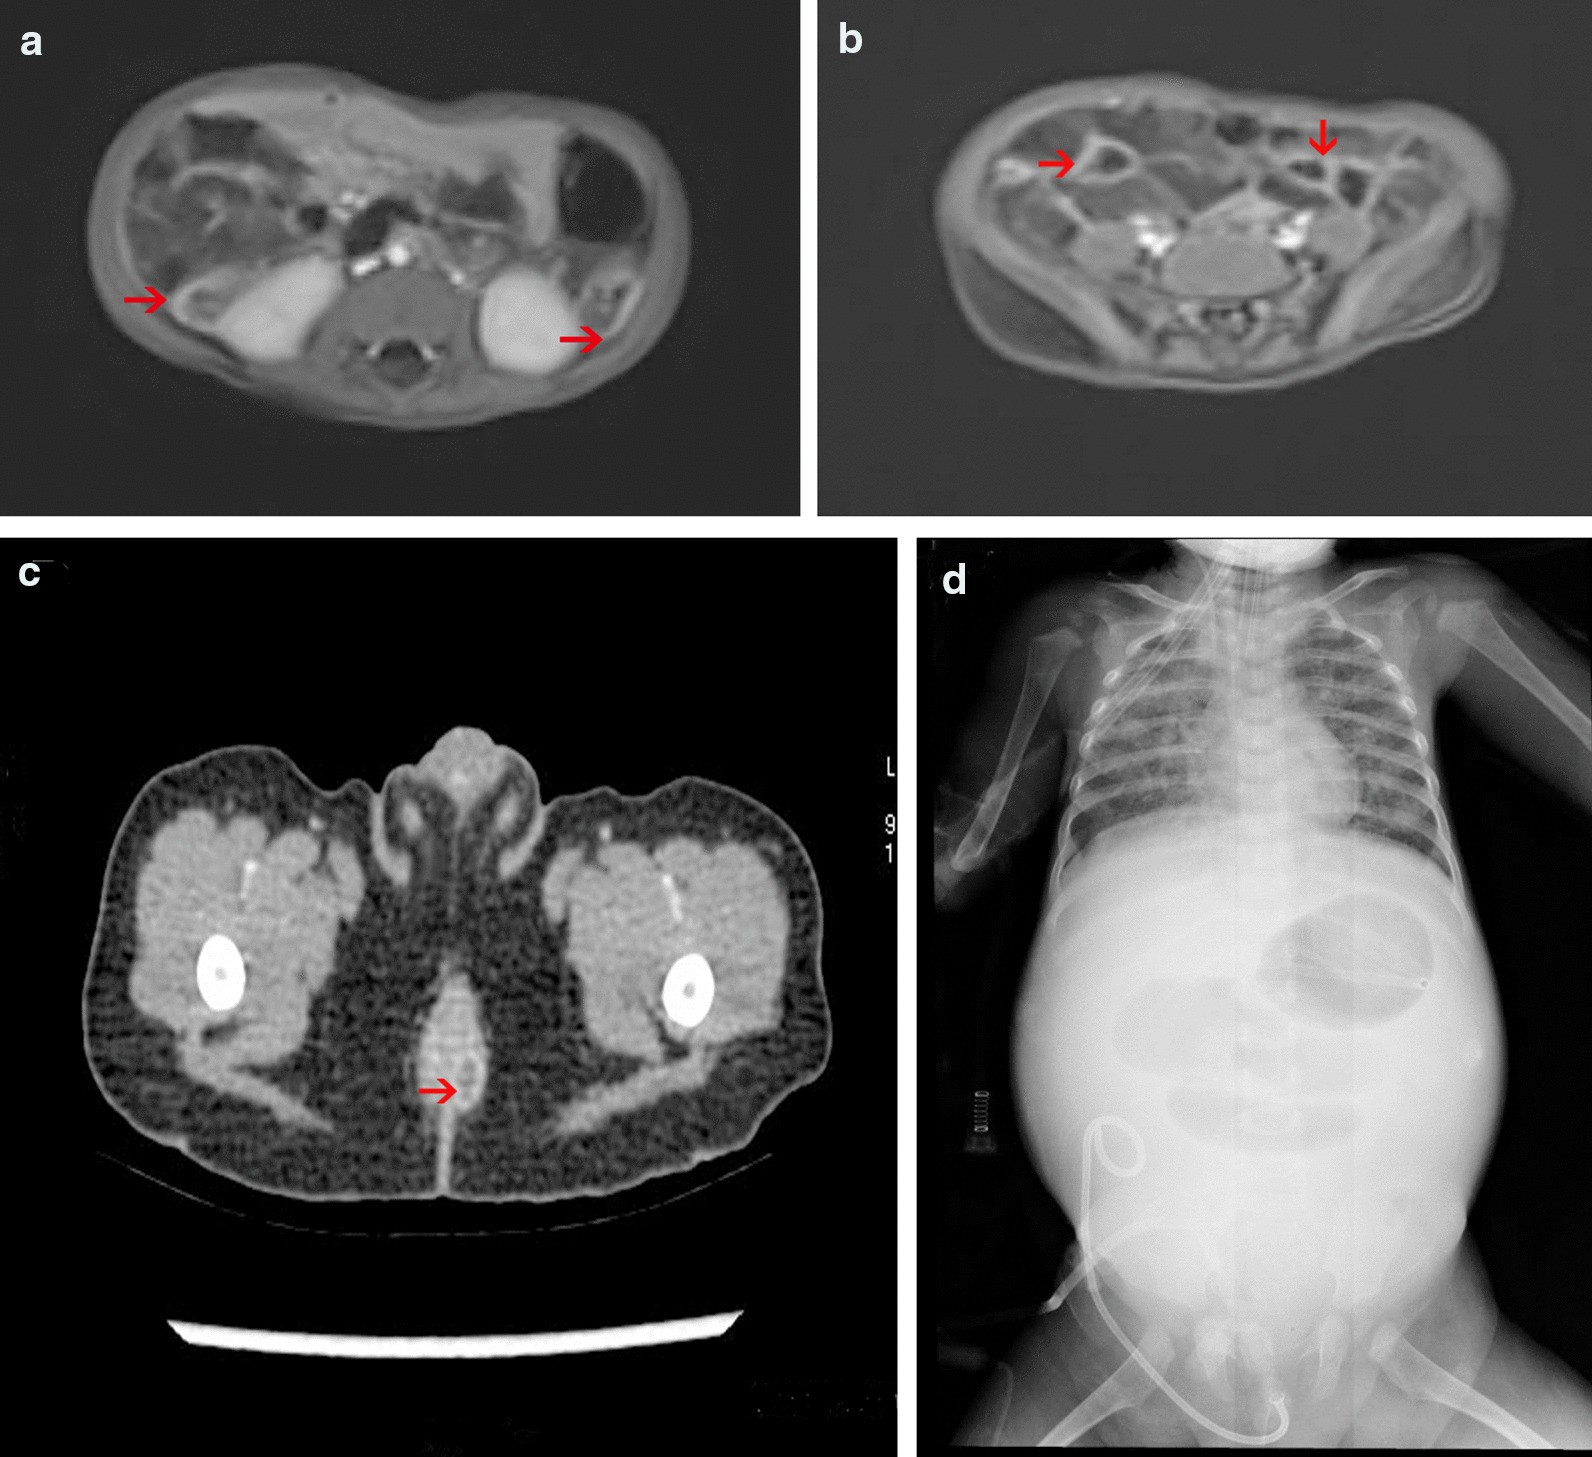

Fig. 2

Imaging examination of VEOIBD patients with IL10RA gene mutations. a High signal of the colon in the abdominal MRI image of case 1. b High signal of the small bowel in the abdominal MRI image of case 1. c Perianal abscess in the enhanced CT image of case 3. d Intestinal obstruction and necrosis on X-ray examination in case 3